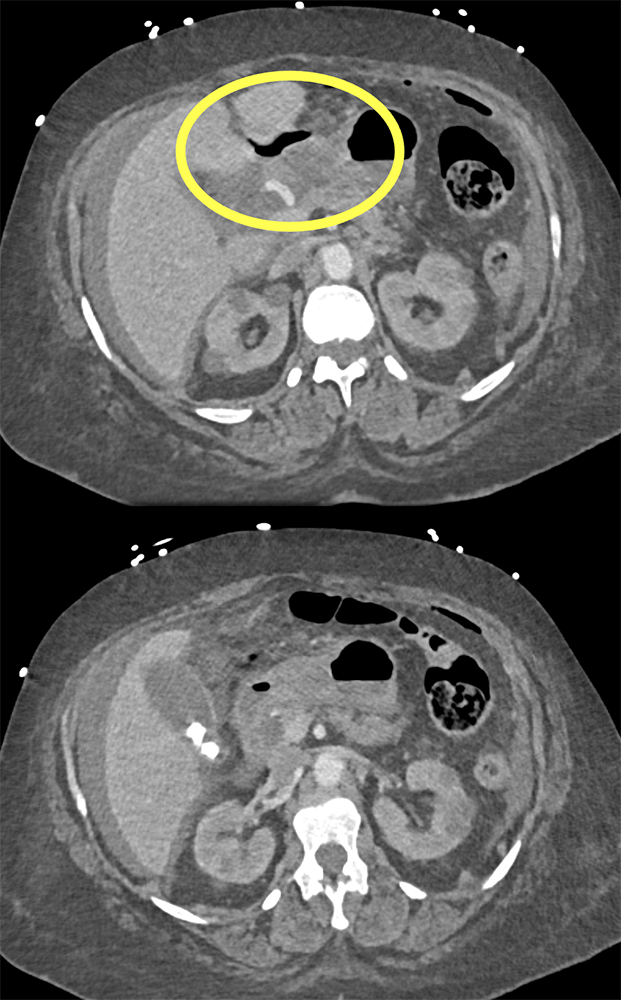

“In our patient, the findings of prominent mucosal folds extending from the pylonic channel on upper gastrointestinal series and the thickened antral wall on CT scans correlate well with the known pathologic appearance of gastnic antral vascular ectasia. Histologically, antral thickening results from a combination of foveolar and fibromuscular hyperplasia. Grossly, the antral fold prominence appears to result from bunching of the mucosa in the thickened, hypercontractile antrum.” Gastric antral vascular ectasia ("watermelon stomach"): radiologic findings. Urban BA, Jones B, Fishman EK, Kern SE, Ravich WJ. Radiology. 1991 Feb;178(2):517-8. |

“Gastric antral vascular ectasia primanily affects women (9:1 female-to-male ratio) aged 56-76 years, and is associated with liver cirrhosis (37%) and achlorhydnia (35%). The usual symptoms are iron-deficiency anemia and melena due to chronic gastrointestinal bleeding from the dilated, superficial, and easily traumatized vessels. Antrectomy is curative, but endoscopic treatment with heat probes or lasers has shown promise.” Gastric antral vascular ectasia ("watermelon stomach"): radiologic findings. Urban BA, Jones B, Fishman EK, Kern SE, Ravich WJ. Radiology. 1991 Feb;178(2):517-8. |